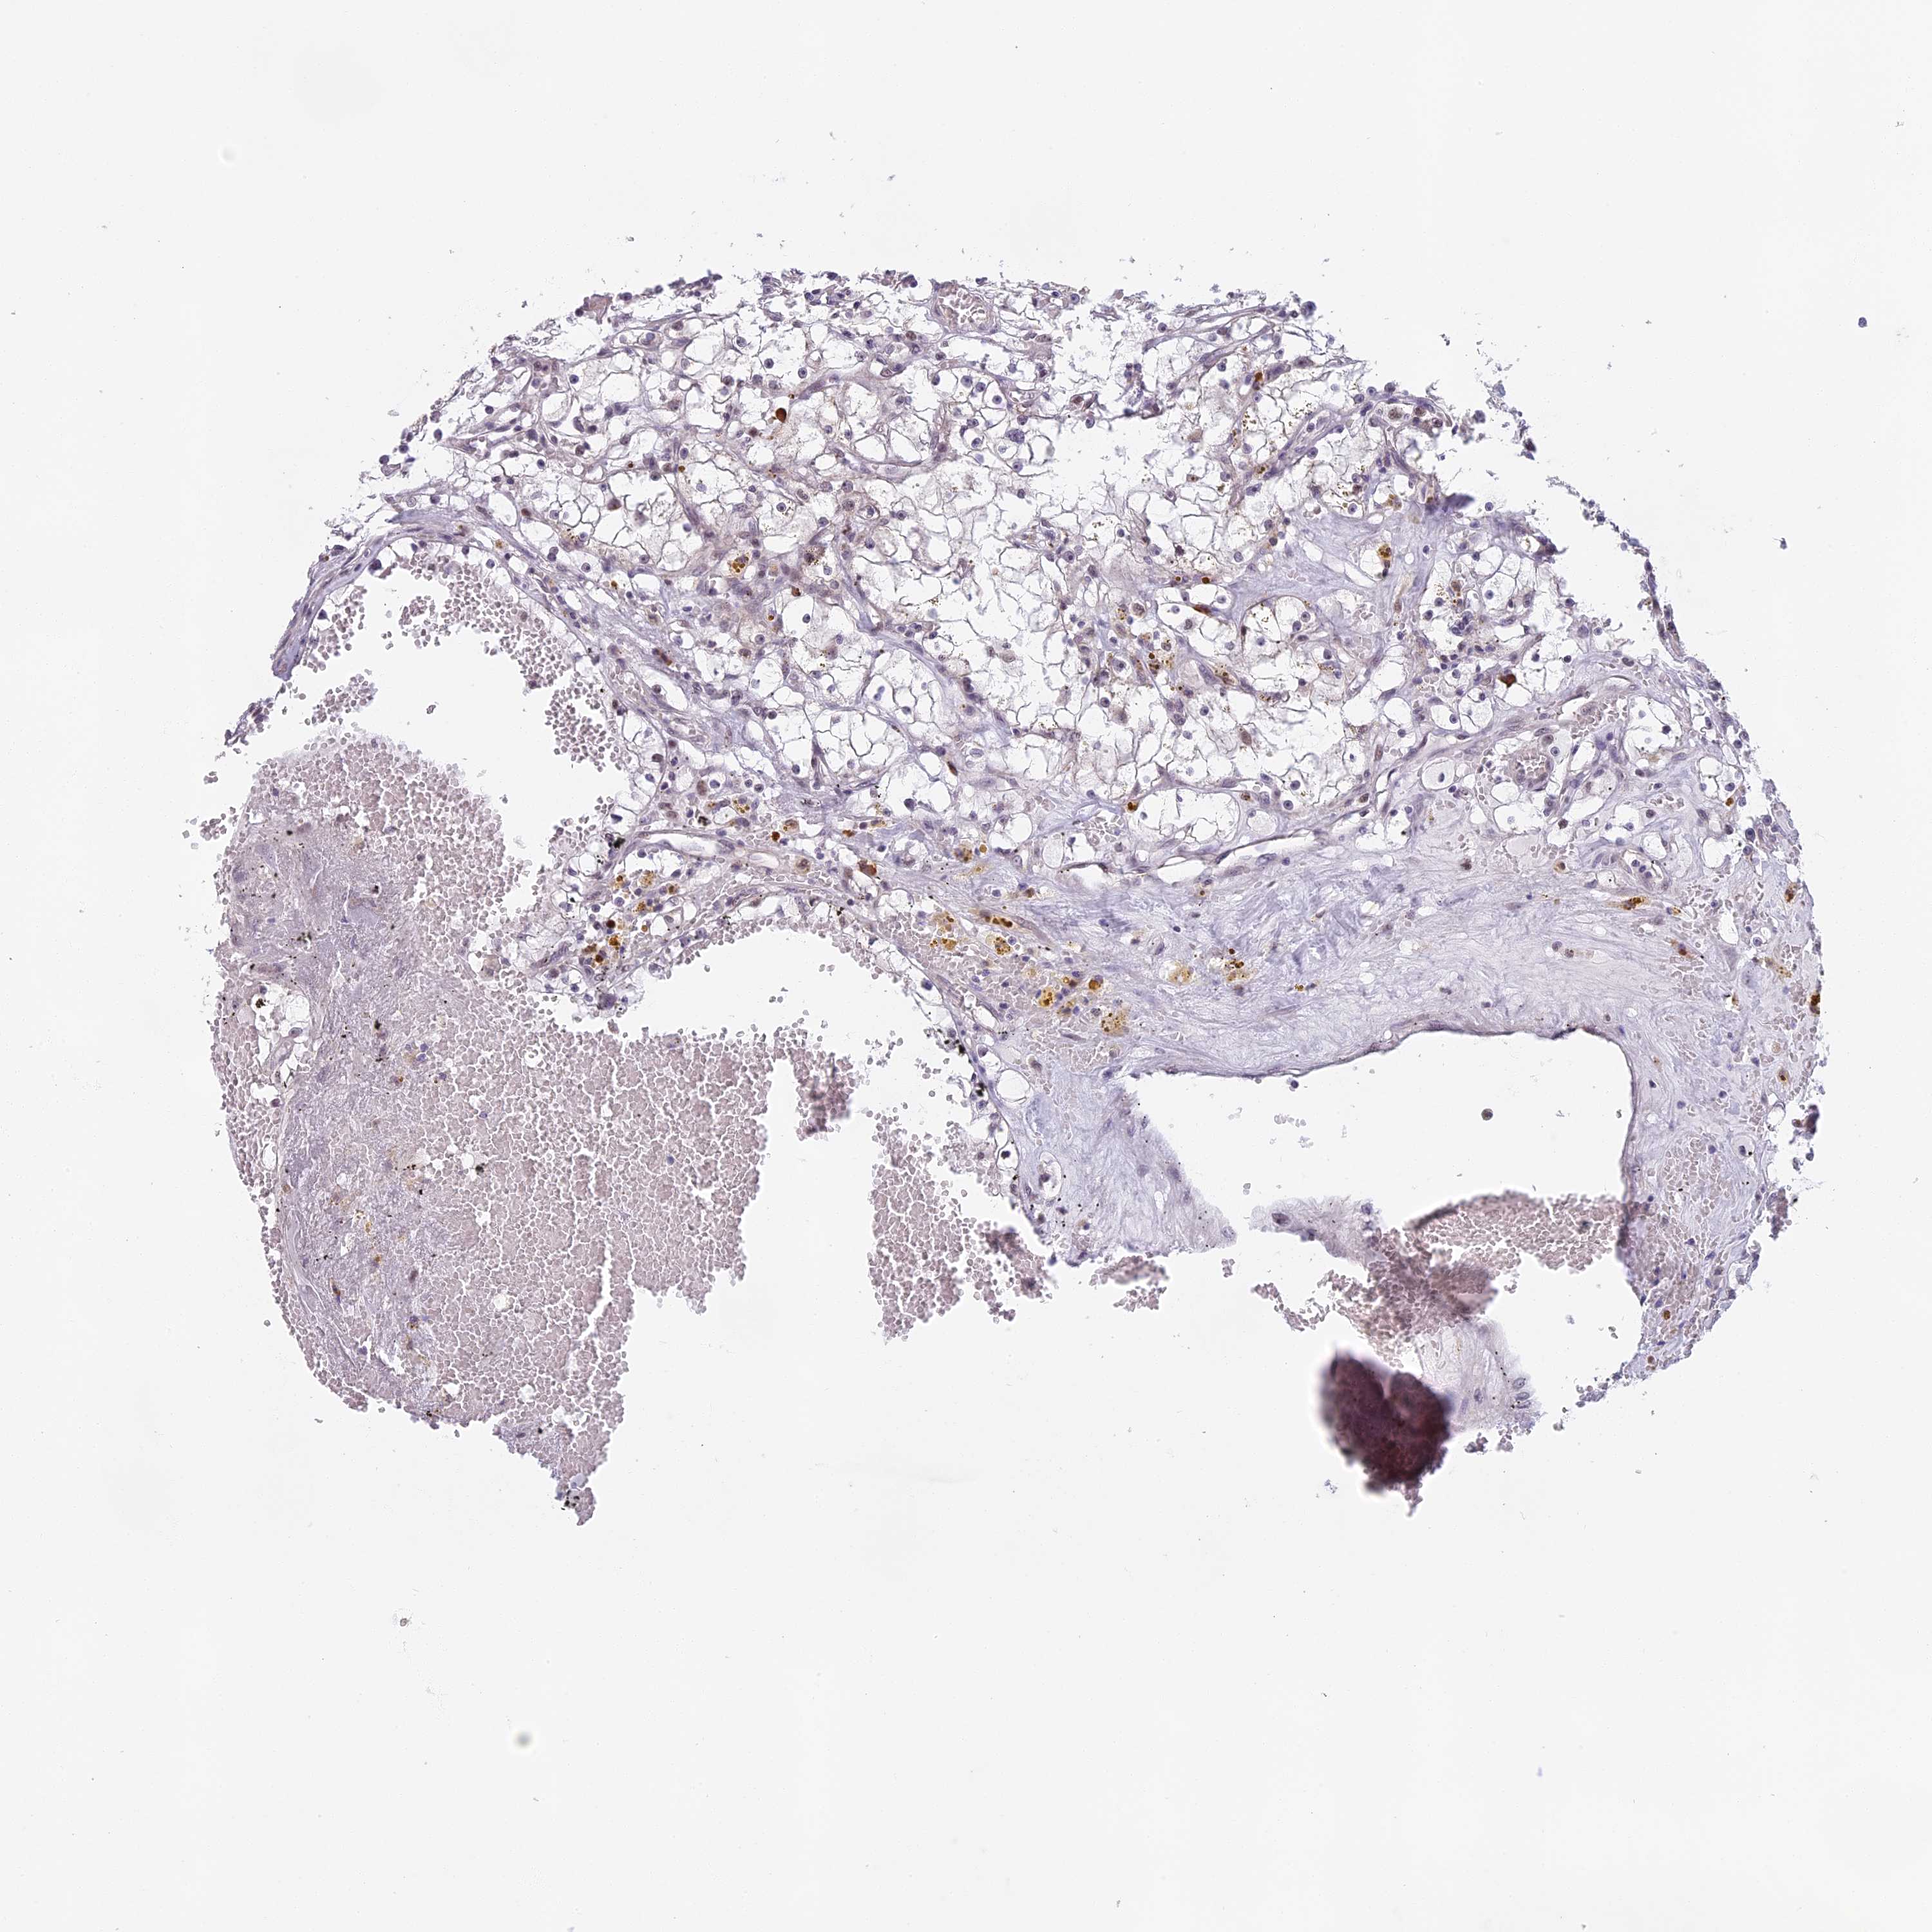

KIDNEY RENAL CLEAR CELL CARCINOMA (VALIDATION) - Interactive survival scatter ploti

The Survival Scatter plot shows the clinical status (i.e. dead or alive) for all individuals in the patient cohort, based on the same data that underlies the corresponding Kaplan-Meier plots. Patients that are alive at last time for follow-up are shown in blue and patients who have died during the study are shown in red.

The x-axis shows the expression levels (FPKM) of the investigated gene in the tumor tissue at the time of diagnosis. The y-axis shows the follow-up time after diagnosis (years). Both axes are complimented with kernel density curves demonstrating the data density over the axes. The top density plot shows the expression levels (FPKM) distribution among dead (red) and alive patients (blue). The right density plot shows the data density of the survived years of dead patients with high and low expression levels respectively, stratified using the cutoff indicated by the vertical dashed line through the Survival Scatter plot. This cutoff is automatically defined based on the FPKM cutoff that minimizes the p-score. The cutoff can be changed by dragging the vertical line or by entering a cutoff value in the square labeled "Current cut-off".

Under the Survival Scatter plot the p-score landscape (black curve; left axis) is shown together with dead median separation (red curve; right axis). Dead median separation is the difference in median mRNA expression between patients who have died with high and low expression, respectively. It is calculated as follows: median FPKM expression of dead patients with high expression - median FPKM expression of dead patients with low expression. This is intended to aid the user in visually exploring custom cutoffs and the associated p-scores and dead median separation.

Individual patient data is displayed and can be filtered by clicking on one or more of the category buttons on the top of the page. Categories describing expression level and patient information include: high, low, alive, dead, female, male and tumor stages. The scale of the x-axis can be toggled between linear and log-scale by clicking on the "x log" button. Mouse-over function shows TCGA ID, patient information and mRNA expression (FPKM) for each patient.

& Survival analysisi

Kaplan-Meier plots summarize results from analysis of correlation between mRNA expression level and patient survival. Patients were divided based on level of expression into one of the two groups "low" (under cut off) or "high" (over cut off). X-axis shows time for survival (years) and y-axis shows the probability of survival, where 1.0 corresponds to 100 percent.

MORF4L1 is validated prognostic, high expression is favorable in Kidney Renal Clear Cell Carcinoma (validation)

Best expression cut offi

Based on the FPKM value of each gene, patients were classified into two groups and association between prognosis (survival) and gene expression (FPKM) was examined. The best expression cut-off refers the FPKM value that yields maximal difference with regard to survival between the two groups at the lowest log-rank P-value. Best expression cut-off was selected based on survival analysis .

When clicking on this number, the vertical dashed line indicating cut-off, the interactive survival plot, and the Kaplan-Meier curve will be adjusted to show results based on the best expression cut-off.

: 270.28

Average pTPM 314.2

Number of samples 100